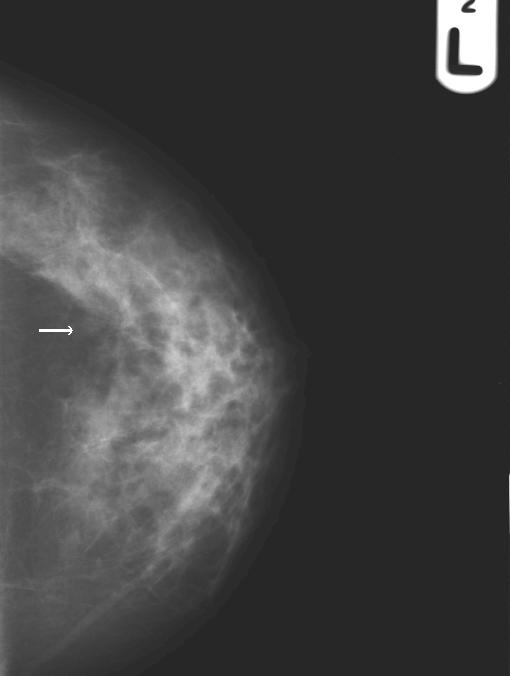

Breast Scan GIF #2

Breast Scan GIF #1

• Breast compression is essential for stopping movement and reducing radiation dose during mammography, but can we use it to also tell if the tissues in the breast are soft or hard or fixed or mobile? See the movies. And, what effect does breast compression have on contrast-enhanced digital mammo and background parenchymal enhancement?